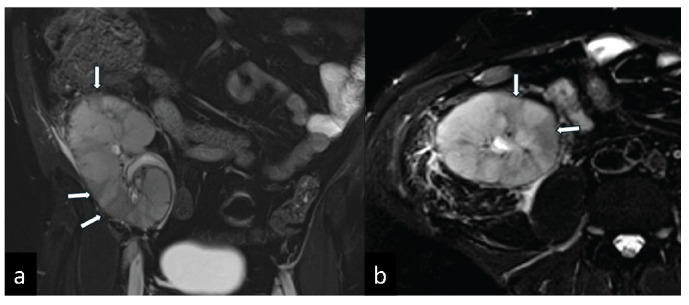

因子V Leiden杂合突变和高同型半胱氨酸血症表现为血管排斥和同种异体肾移植梗死。

Factor V Leiden Heterozygous Mutation and Hyperhomocysteinemia Presenting with Vascular Rejection and Renal Allograft Infarction.